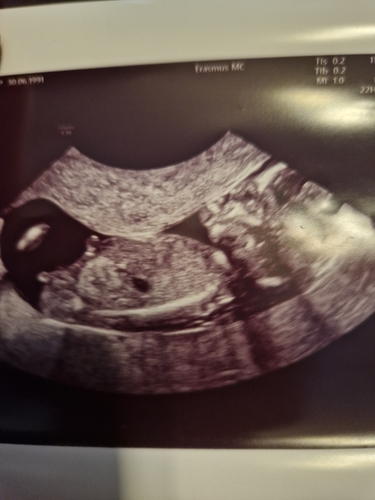

Vandaag de 13 weken echo gehad met 13+1 wat denken jullie

🩷